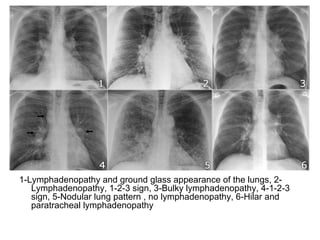

1-Lymphadenopathy and ground glass appearance of the lungs, 2-

Lymphadenopathy, 1-2-3 sign, 3-Bulky lymphadenopathy, 4-1-2-3

sign, 5-Nodular lung pattern , no lymphadenopathy, 6-Hilar and

paratracheal lymphadenopathy